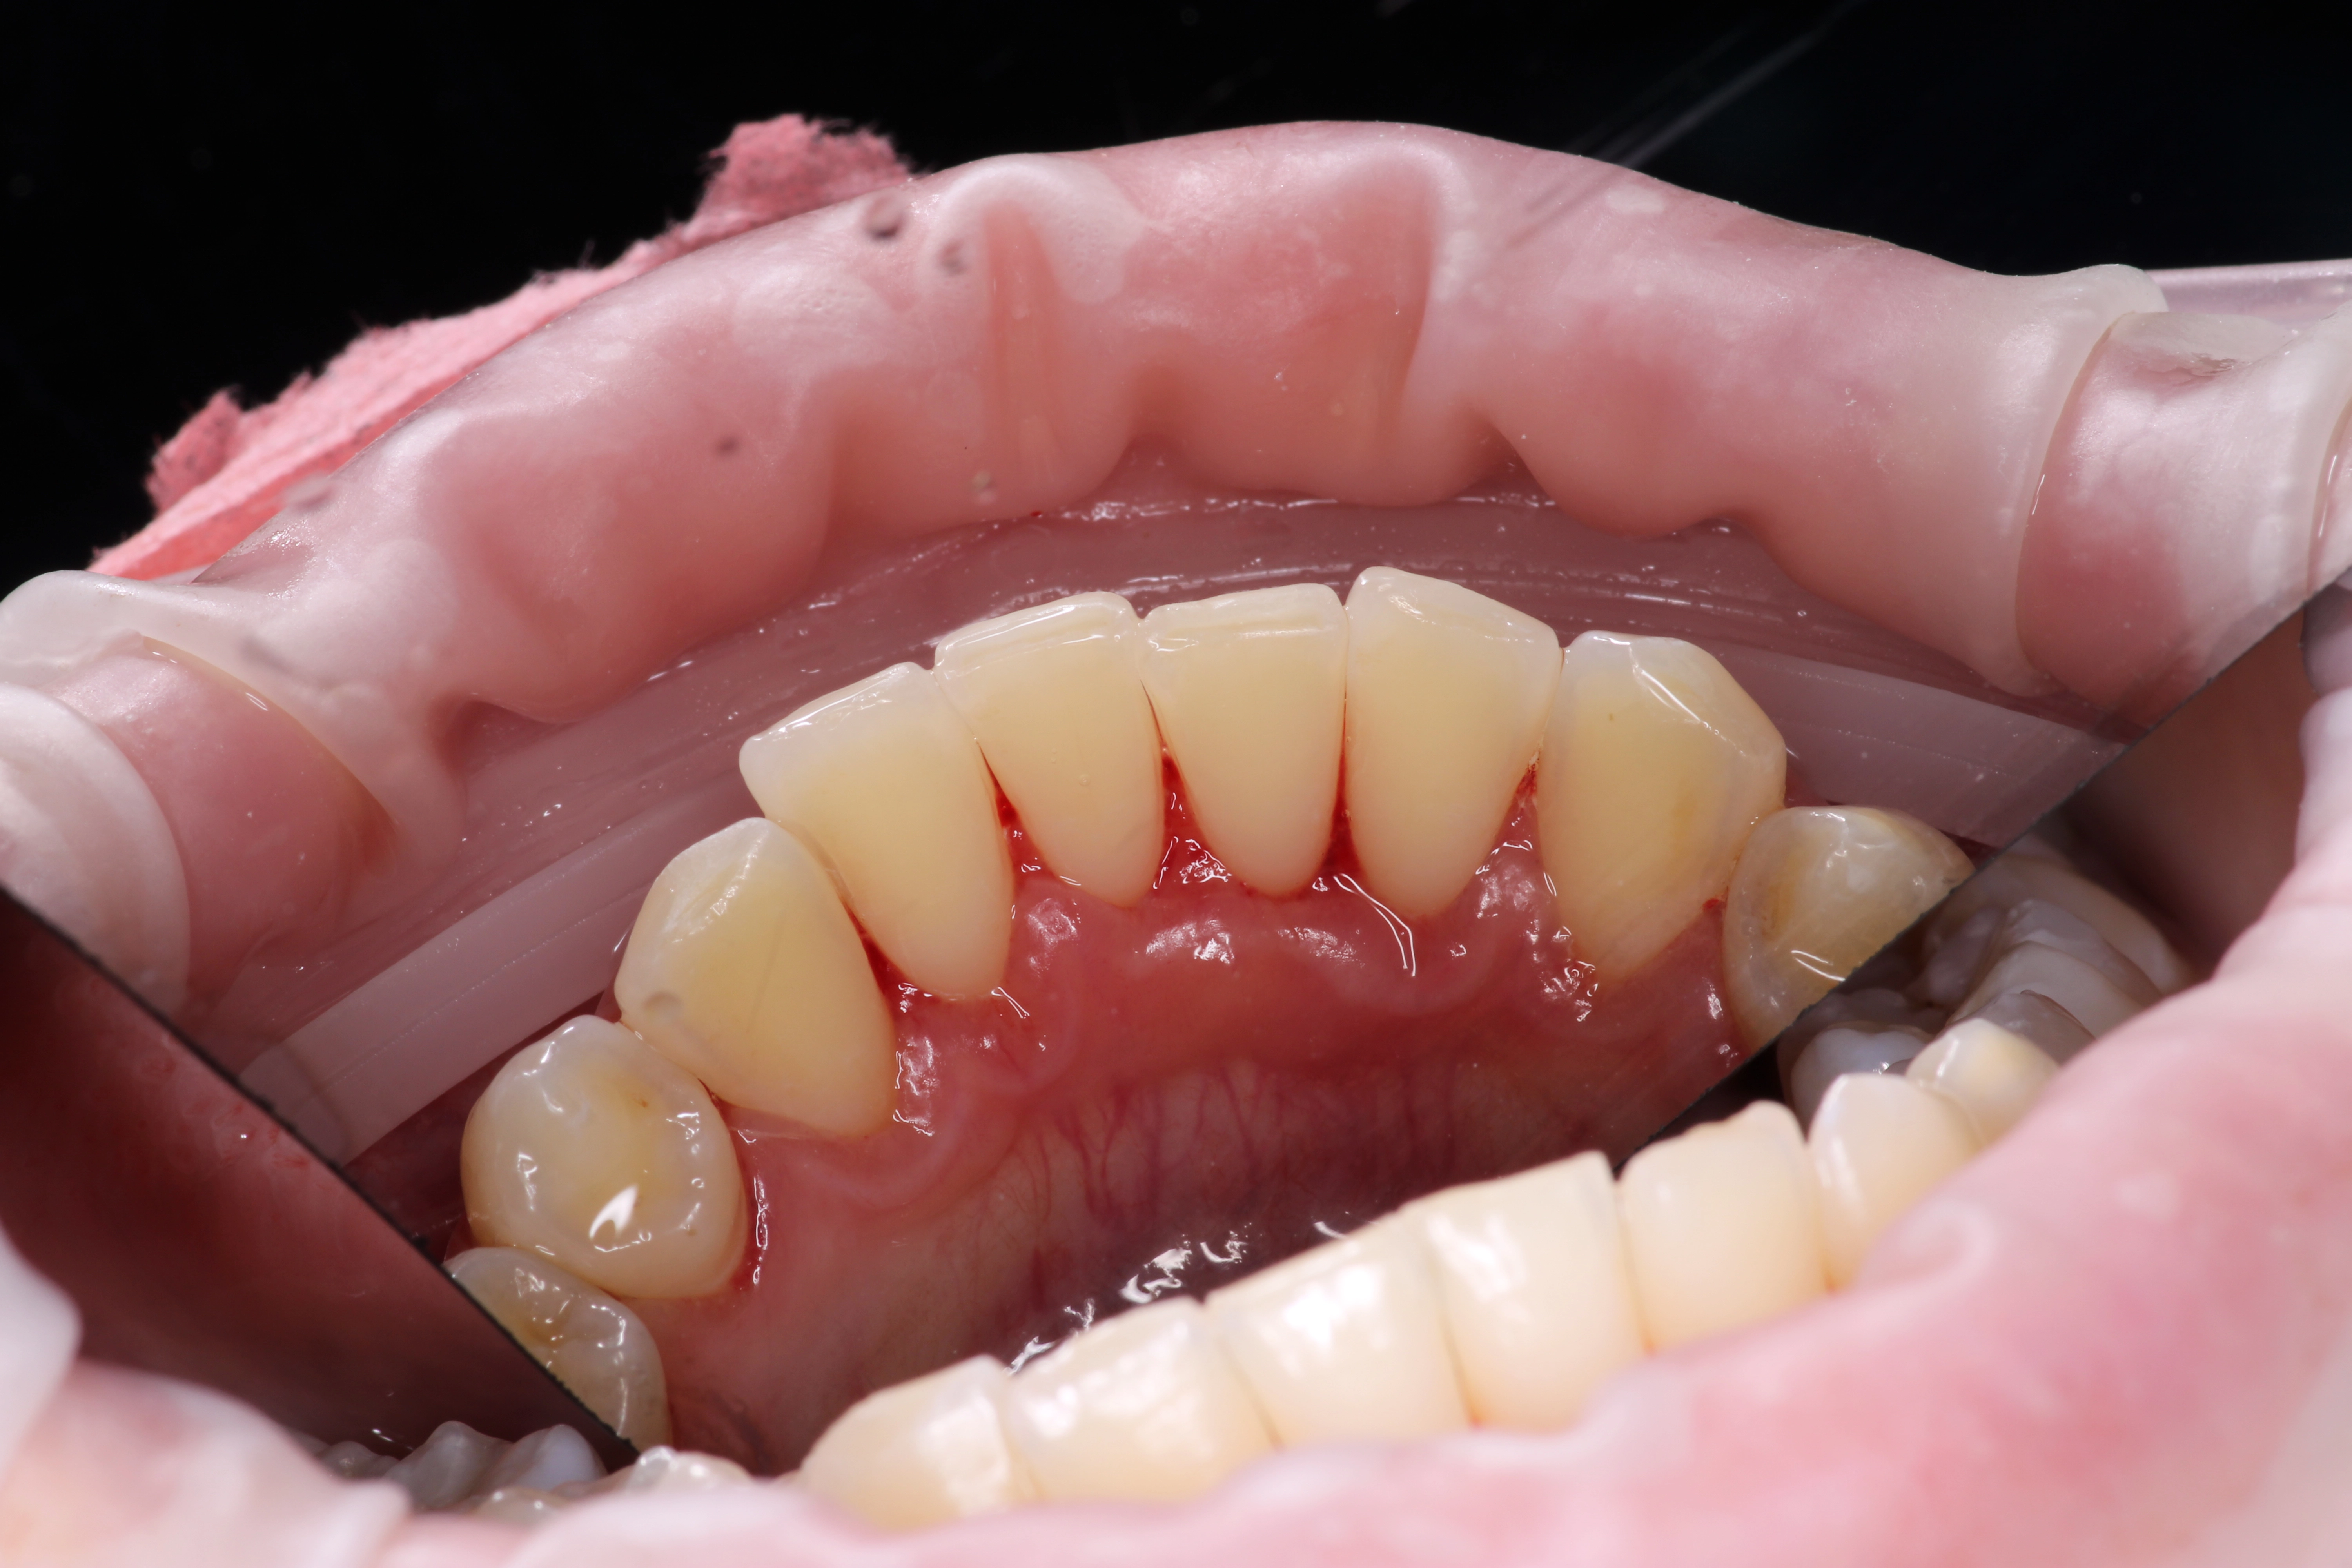

Пародонтит легкой степени

• Визуально заметен мягкий зубной налет и твердые зубные отложения

• Воспаление края десны: десна становится ярко-красной или синюшной

• Кровоточивость десен при чистке зубов

• На рентгенограмме заметно начальное рассасывание костной ткани

• Пародонтальные карманы увеличены на 1,5-2 мм